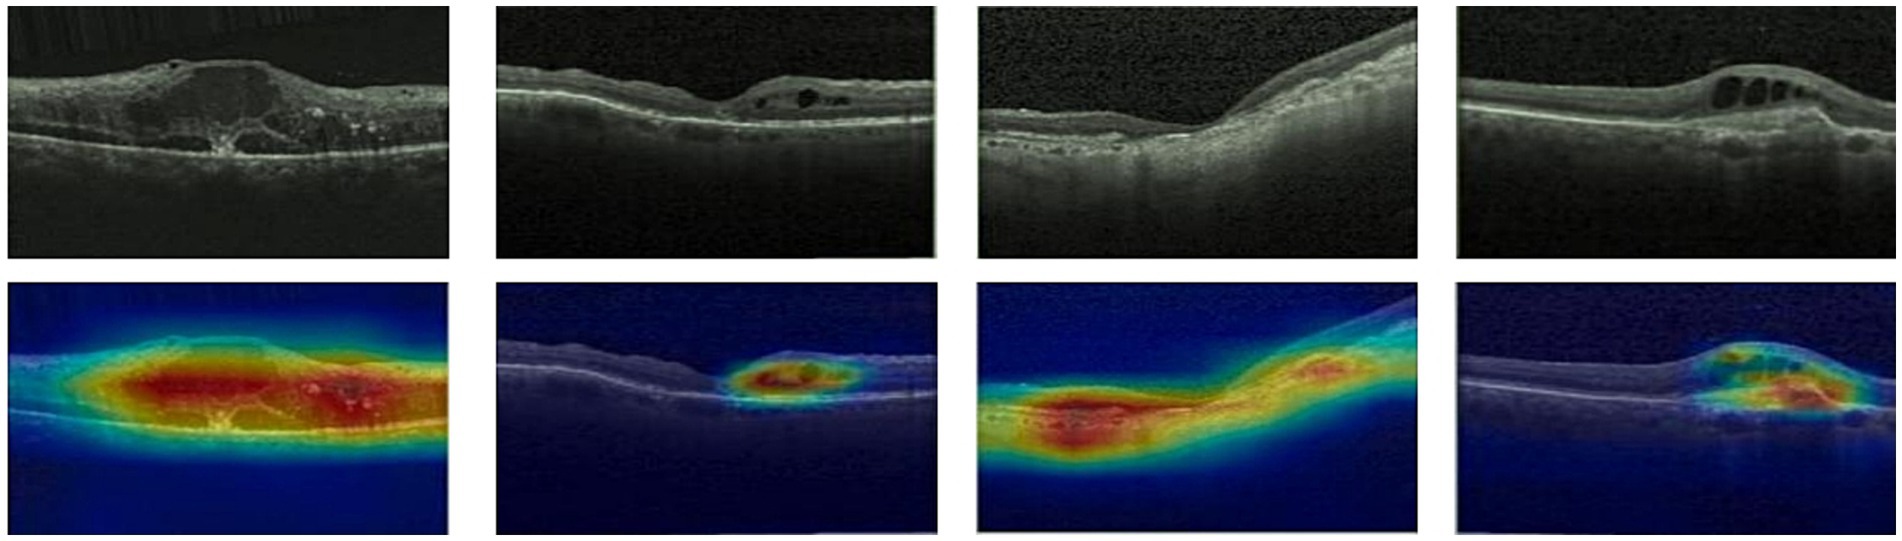

3.4 Features map visualization

Given ethical considerations and direct impact on human life and health, the interpretability of deep learning models could help clinicians, patients, and researchers in comprehending, trusting, and efficiently employing artificial intelligence technologies in the healthcare domain. In this section, we utilized the Grad-CAM method (38) to present Class Activation Mapping (CAM) visualizations, which could demonstrate the evidence underlying the predictions of the proposed model. The heat maps were generated by the CAM technique to emphasizes specific regions in an OCT image that were closely linked to the target class. The Grad-CAM showed the regions of interest. As shown in Figures 8, 9, 10, the Grad-CAM were generated based on original OCT images. Deeper red color represented stronger correlation with the predicted category. From the Grad-CAM, we found that the lesion regions were all appear with red. It demonstrated that the model payed attention to the crucial regions, which aligned with the diagnostic process of ophthalmologists.

Figure 9

Features map visualization of HyReti-Net on OCT-2017 dataset. The first line is the original OCT images. The second line is class activation mapping visualizations based on Grad-CAM method.

For each public dataset, heatmaps were also generated to enhance the interpretability of OCT image classification, as shown in Figures 8, 9, 10. The heatmaps showed the specific regions in an OCT image that were closely linked to the target class. It meant that HyReti-Net was able to accurately focus on the lesion area, which meant that the corresponding classification performance was better.